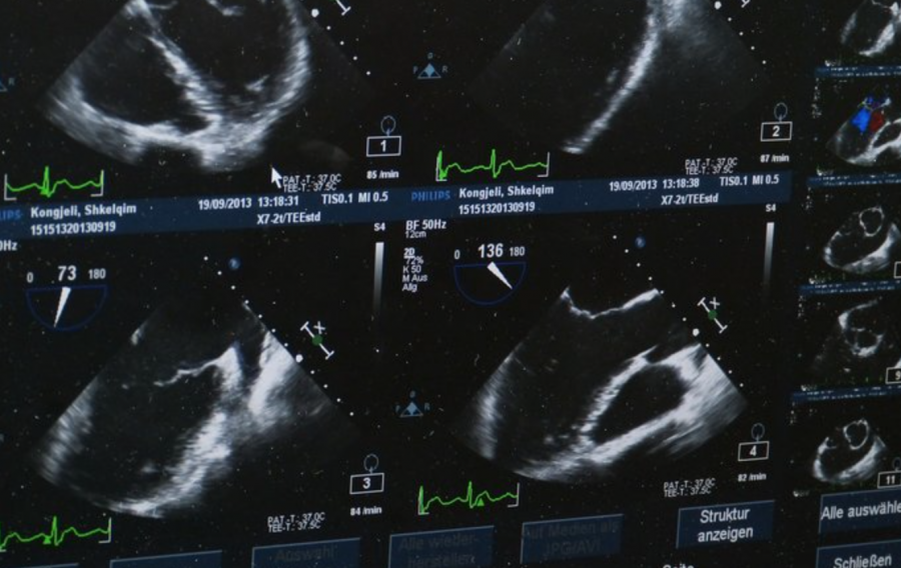

Спасти ситуацию помогли двухмерные фазированные датчики. Чтобы уменьшить число проводов в кабеле датчика, внутрь самого датчика поместили целый высокопроизводительный компьютер, который «сжимает» полученные данные и пересылает их в закодированном виде по относительно тонкому кабелю. Благодаря этому удается получать частоту несколько десятков «объемов» в секунду. А этого уже достаточно, например, для полноценной визуализации сердца в реальном времени. Поскольку к трем пространственным измерениям добавляется полноценное четвертое, время, эти технологии получили название 4D-УЗИ. С их помощью можно строить полноценное изображение клапанов сердца в режиме реального времени. Его примери приведен ниже.